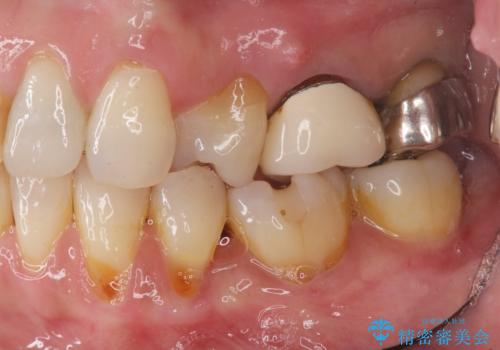

自然な仕上がりのブリッジ治療を達成することができ満足いただくことができました。

セラミック治療の注意事項(リスク・副作用など)

- 天然歯を削ります

- 硬い素材は天然歯を傷つけてしまう場合があります

- かみ合わせや歯ぎしりが強すぎる方はセラミックが割れてしまう可能性があります

- 自費診療(保険適用外治療)となります